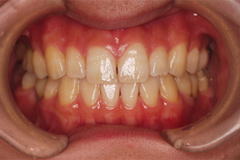

1.矯正治療で隙間をなくす}

2.インプラント治療

3.マウスピースによる咬合改善維持

4.定期的な予防治療(PMTC)

歯がない期間が長く続いたため隣の歯が横に倒れてしまい、歯と歯との間に隙間が2ケ所できてしまっていたため、インプラントの前に矯正治療で隙間をなくす治療を行う